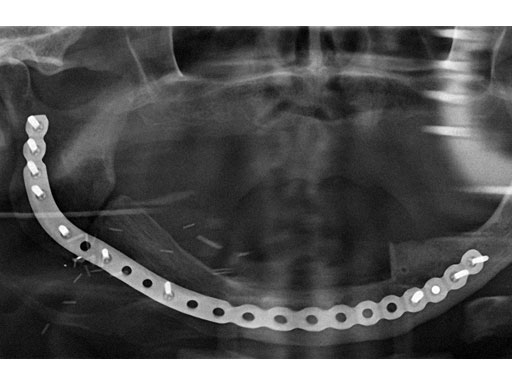

Fig 2

ab Preoperative radiograph and MRI.

c Postoperative radiograph.

Case provided by Christoph Pautke, Mnchen, Germany